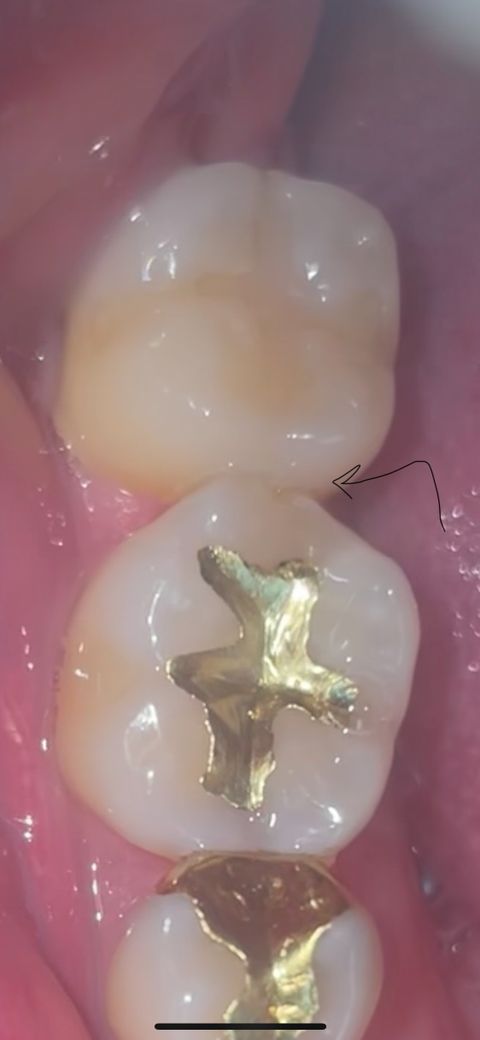

치아파절 어떻게 치료가 가능할까요?

사진처럼 어금니 사이에 홈을 발견했습니다

앞 어금니가 모서리 부분이 깨지면서 그 사이에 음식물이 꼈던거 같네요 요 며칠간 잇몸이 지끈거리고 아파서 치실 치간칫솔을 해줬더니 피가 나고 통증이 많이 내려가더군요 (치간칫솔 치실할때 많이 아프네요 ㅠ) 치실을 소홀히 해서 생긴 염증일까요 ㅠ 저렇게 놔두면 다시 음식물이 끼고 염증이 생길거 같은데 어떻게 치료를 해야할까요 가능할까요?

또 인접면에 하얗게 보이는 것은 충치인가요? 충치도 치료가 필요할지 궁금합니다

• 1번 째 사진

사진과 같은 파절은 매우 작게 깨진 부위이기 때문에 레진이라는 재료로 간단하게 충전이 가능할 것으로 생각됩니다.

인접면이 떨어져서 공간이 생기고 해당 부분으로 음식물이 낀다면 레진으로 수복하거나 인레이로 수복해주어야 합니다. 어떻게 치료하는게 유리할지는 치과 방문 후 선생님과 상담이 필요해보입니다.

정확한건 엑스레이를 찍어 보셔야되겟지만 많이 깨졋다면 인레이 치료를 하셔야될수도 있습니다.

모서리 깨진 부위로 음식물이 잘 낀다면 떼우는 치료를 해주는 것이 좋을 것 같습니다 더 깨져나가거나 충치가 생길 수 있습니다

하얗게 보이는 것은 백색반점 형태의 초기충치의 양상일 수 있습니다